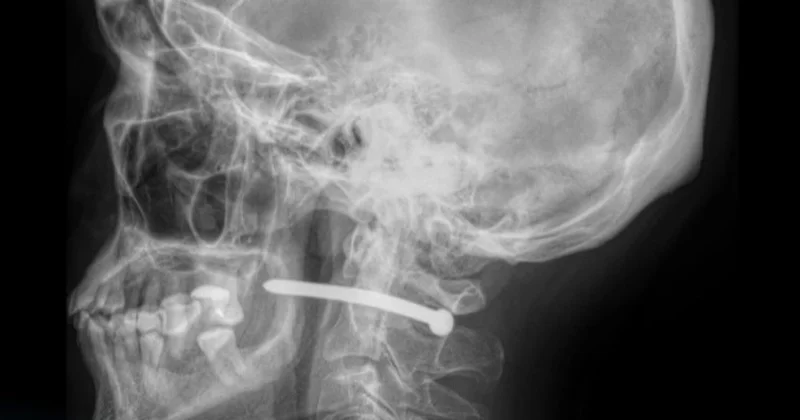

Петропавл қалалық көпбейінді аурухананың мәліметінше, рентгендік зерттеуден кейін пневматикалық пистолетпен атылған шегенің ер адамның құлағының маңына кіріп, мойын омыртқасы жанынан өткені белгілі болды.

Дәрігерлердің айтуынша, маңызды мүшелердің зақымдануына сәл ғана қалған екен.

Жақ-бет хирургтері шегені алып, тиісті ем-дом жасады. Кейін жараны тігіп, науқасты бірқатар ұсыныммен үйге жіберді.

— Мойын тұсынан жарақат алу аса қауіпті. Өйткені мойын арқылы ірі қан тамырлары, жүйке жүйесі, тыныс алу жолы және жұлын өтеді. Саймандармен жұмыс істегенде қауіпсіздің ережесін сақтаған жөн. Қорғаныш заттарын пайдаланып, жарақат алған жағдайда бірден дәрігерге көрінген жөн, — дейді дәрігерлер.